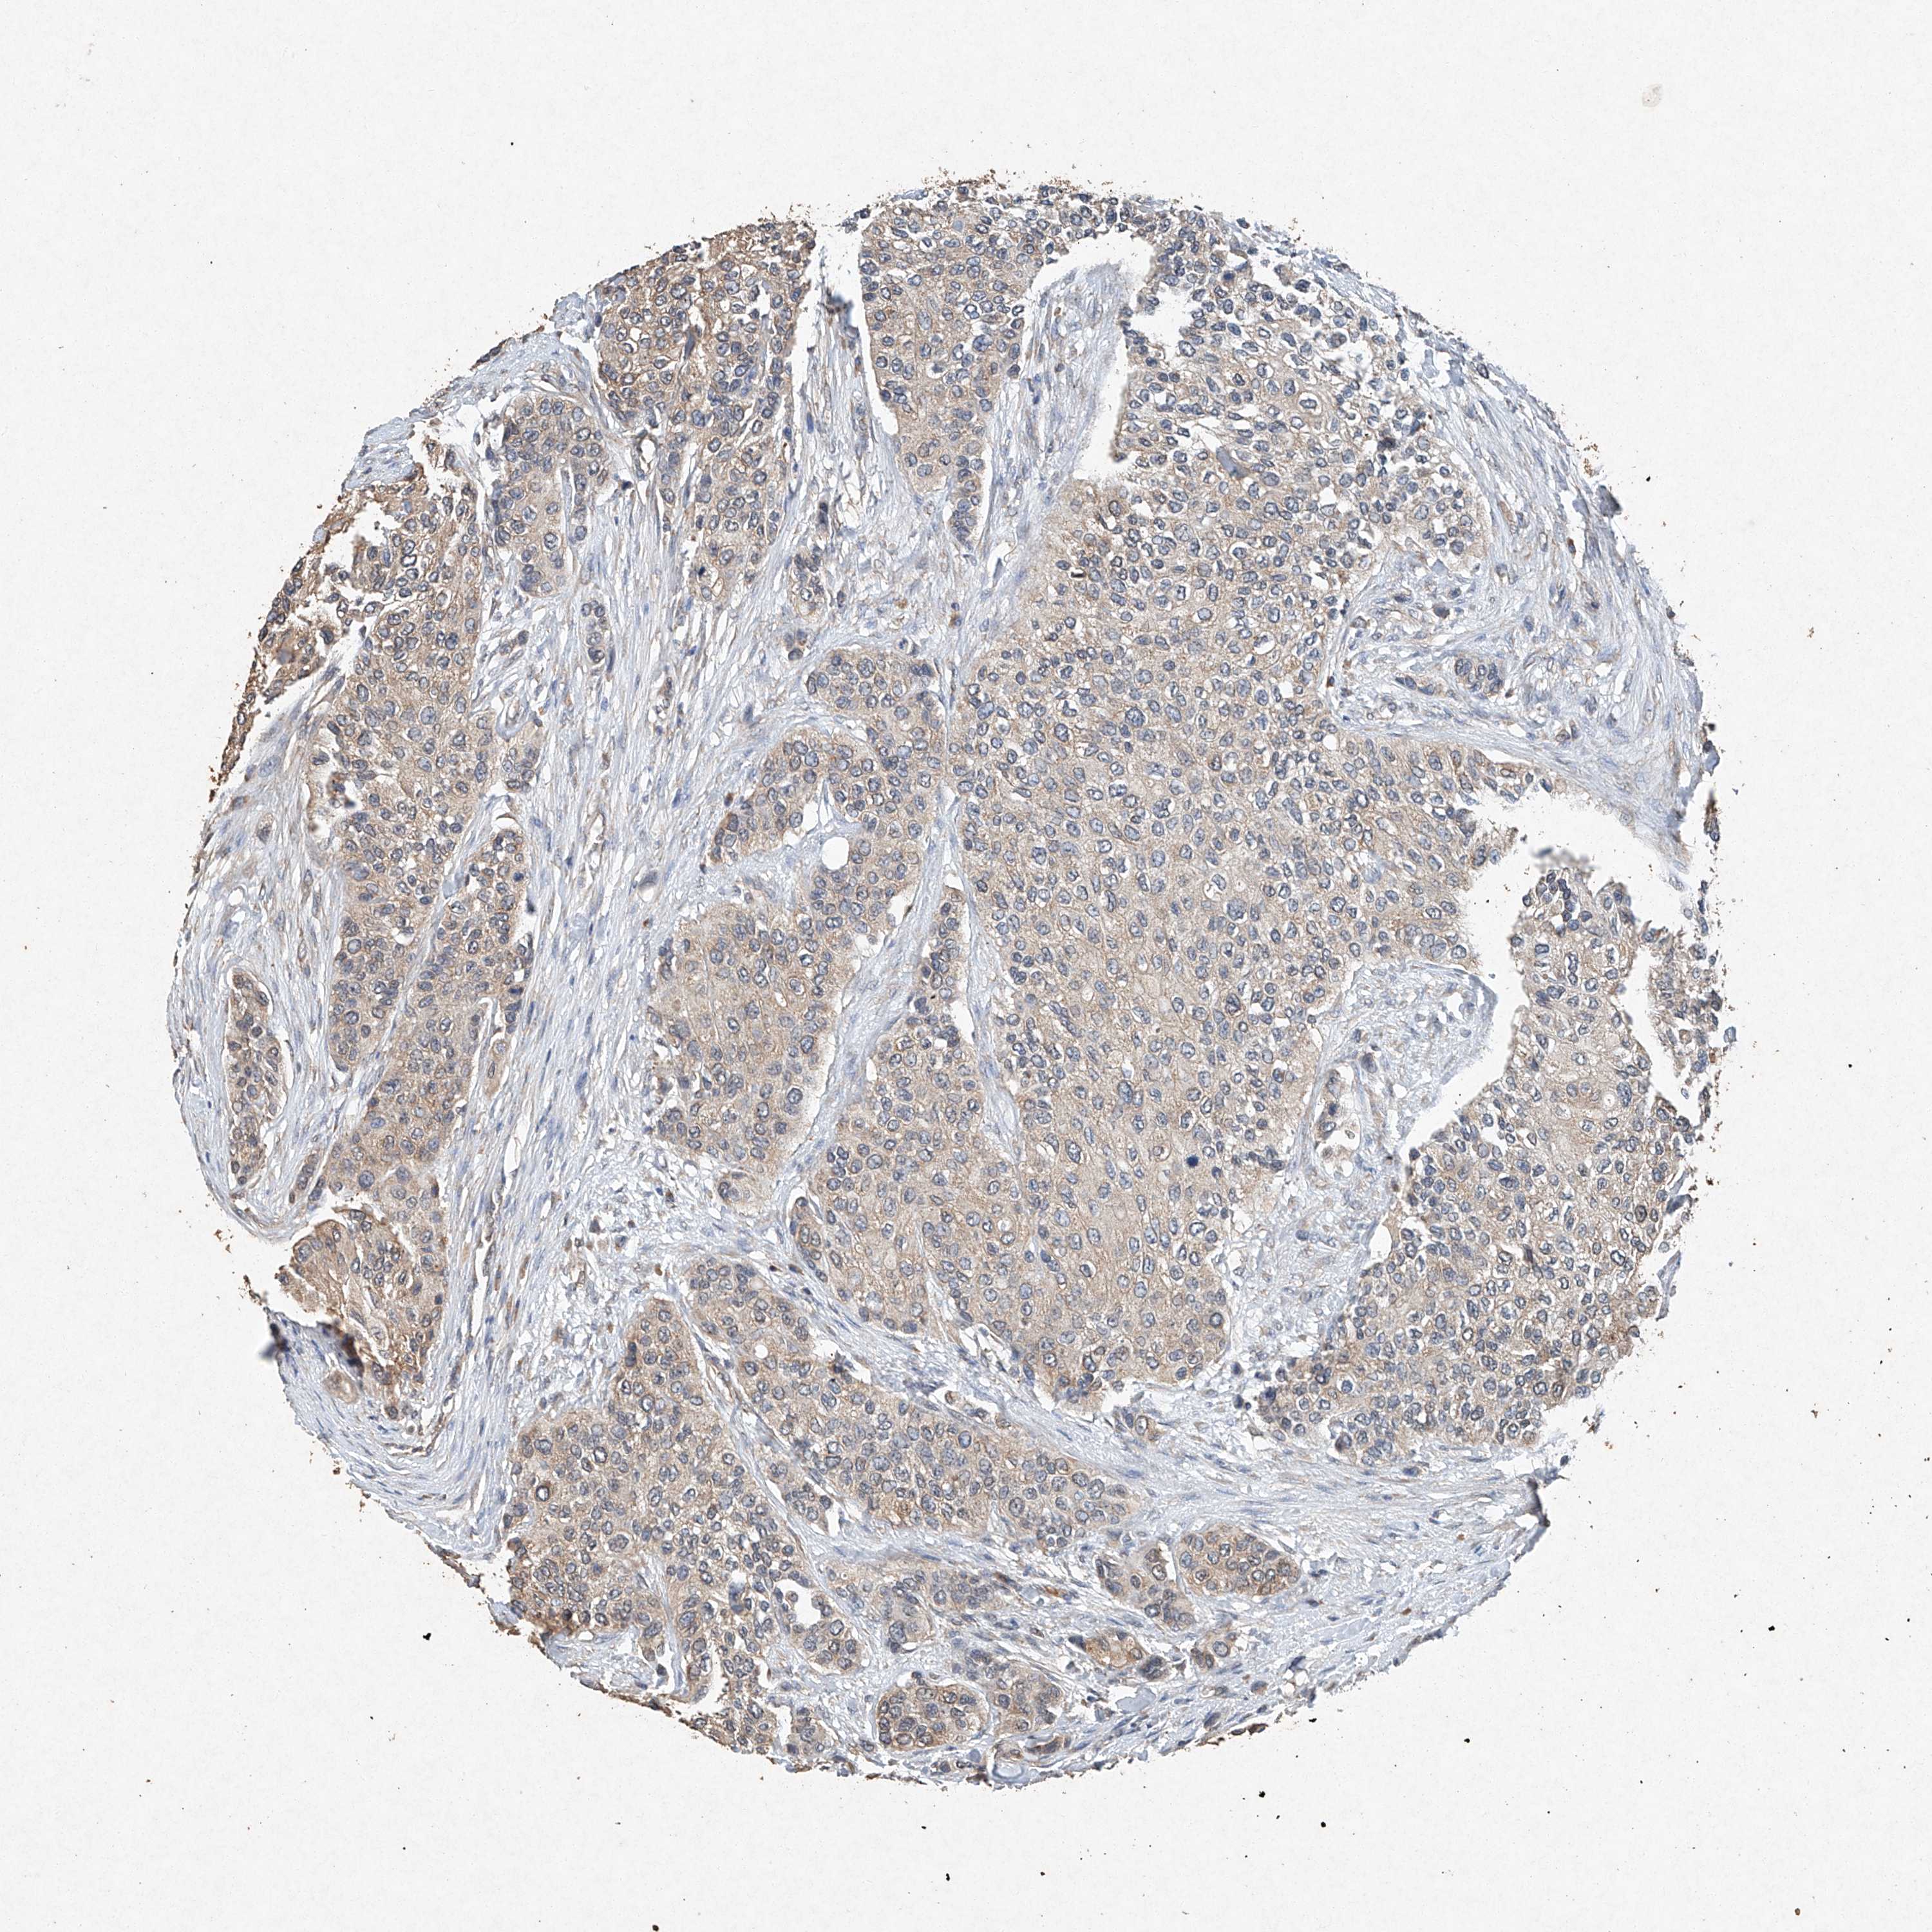

UROTHELIAL CANCER - Protein expressioni

A mouse-over function shows sample information and annotation data. Click on an image to view it in a full screen mode. Samples can be filtered based on level of antibody staining by selecting one or several of the following categories: high, medium, low and not detected. The assay and annotation is described here.

Antibody stainingi

Antibody staining in the annotated cell types in the current human tissue is reported as not detected, low, medium, or high, based on conventional immunohistochemistry profiling in selected tissues. This score is based on the combination of the staining intensity and fraction of stained cells.

Each image is clickable and will lead to virtual microscopy that enables deeper exploration of all samples and also displays staining intensity scores, fraction scores and subcellular localization as well as patient and tissue information for each sample.

Antibody HPA073281

Antibody CAB025316

Staining

High

Medium

Low

Not detected

Intensity

Strong

Moderate

Weak

Negative

Quantity

>75%

75%-25%

<25%

None

Location

Nuclear

Cytoplasmic/membranous

Cytoplasmic/membranous,nuclear

Urothelial carcinoma, High grade